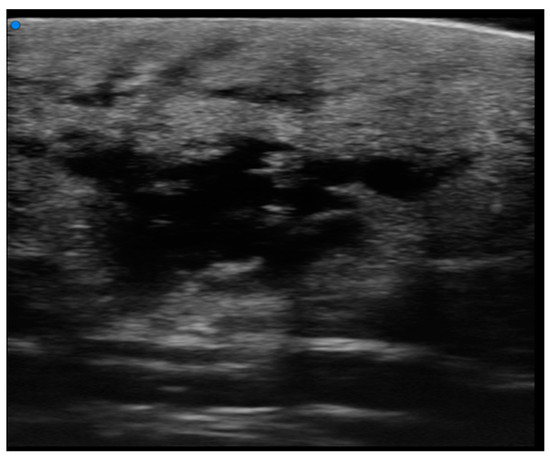

Figure 8. (a) Examination performed with a very high-frequency ultrasound probe at 48 MHz, showing iso-hypoechoic lesions with nodular and multilobulated morphology and irregular margins infiltrating the epidermal and subepidermal tissue at a single point (focal). (b) Reddish, indistinct, slightly exofitic nodule in the lumbar region. Color Doppler analysis showing no significative increase in the signals. Pathological assessment showed B-Cell Lymphoma (recurrence).

Only two lesions exhibited ulceration, manifested as a gap in the epidermal region with thickening of the surrounding dermis. Cutaneous papules were observed on ultra-high frequency ultrasound (UHFUS) as focal infiltrative lesions, and some of them later coalesced to form ill-defined pseudonodules (Figure 8).

Hence, we categorized the lesions as infiltrative focal or nodular lesions, non-infiltrative focal lesions, infiltrative pseudonodular lesions, non-infiltrative pseudonodular lesions, and diffusely infiltrative lesions. Lesions displaying dermal infiltration and irregular margins demonstrated an increase in vascular signal on Doppler integration. Notably, none of the lesions showed calcifications in our study.